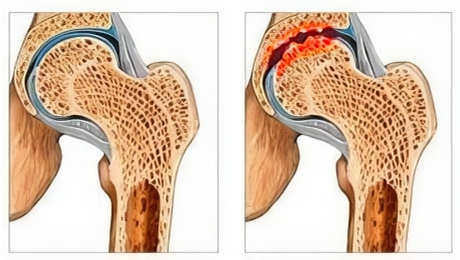

Najczęstszym schorzeniem osób powyżej 50. roku życia jest CHOROBA ZWYRODNIENIOWA STAWÓW, czyli tak zwane zużycie stawów. Większość ludzi ignoruje ten problem, ale z czasem powoduje on nie tylko dolegliwości, lecz także nieodwracalne zniszczenie chrząstki, aż do CAŁKOWITEJ UTRATY STAWU i niepełnosprawności.

Zużycie chrząstki stawowej: w wieku 50–60 lat człowiek może stracić nawet 70% zdrowej chrząstki w kluczowych stawach, co prowadzi do nieodwracalnej utraty stawu i ryzyka niepełnosprawności!

W 92% przypadków osoby w wieku 50 lat mają już liczne uszkodzenia powierzchni chrząstki oraz zmiany zwyrodnieniowe, które najczęściej dotyczą kolan, rąk i kręgosłupa.